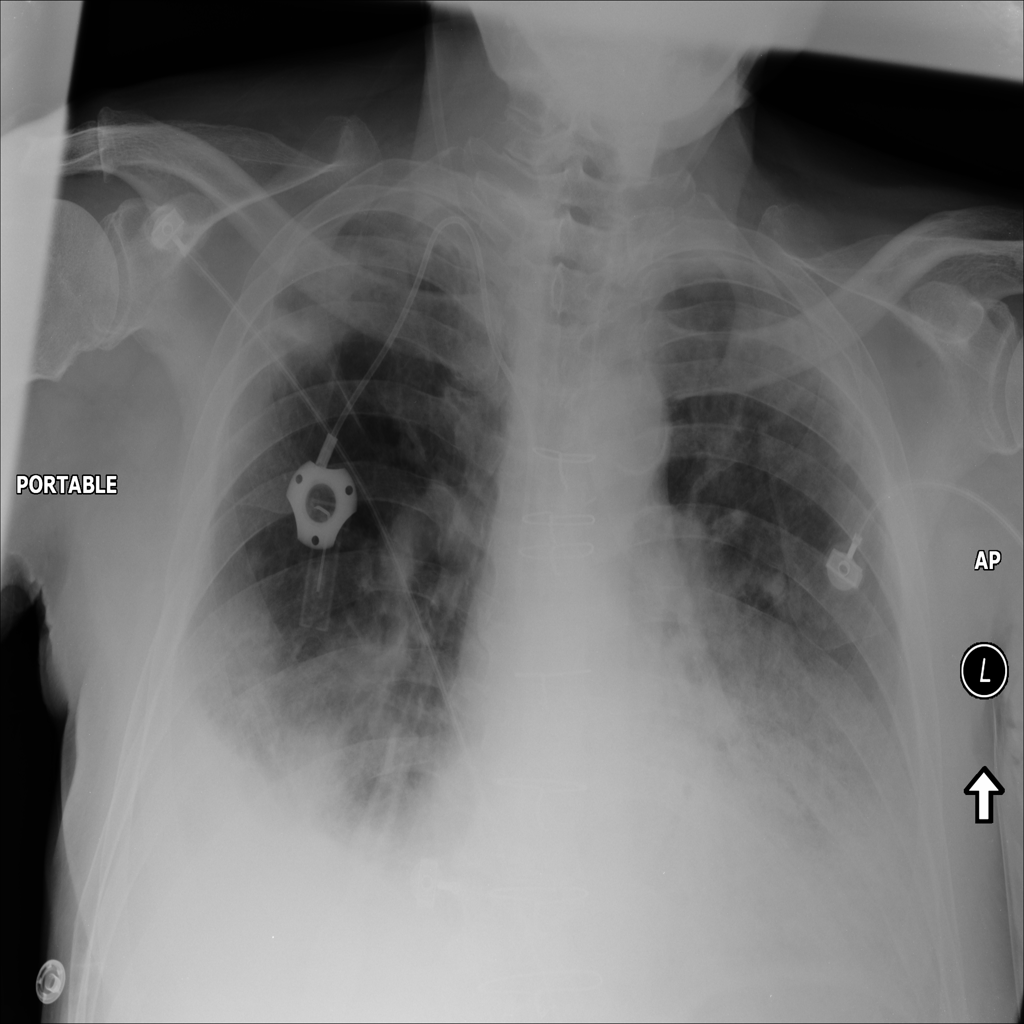

PAT-40F9 · IMG-004Effusion

PAT-40F9 · IMG-004

PA